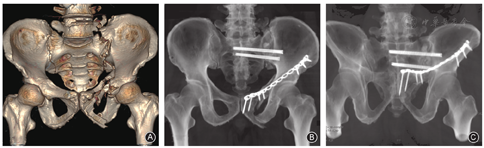

骶髂螺钉可沿钉道轴线均匀分散载荷,是临床公认的治疗骨盆后环损伤的首选方式。骶髂螺钉主要适用于:(1)骶髂关节复合体脱位或骨折脱位;(2)骶骨DenisⅠ、Ⅱ型及部分Ⅲ型骨折;(3)Tile B、C型骨盆损伤;(4)陈旧性骶髂关节脱位或骶骨骨折的截骨矫形;(5)污染相对轻微的骨盆后环开放性损伤;(6)多发伤伴骨盆后环损伤的早期处理;(7)协同髂腰内固定治疗(图3)。

骶髂螺钉的术中定位方法主要包括:(1)"C"型臂X线机透视下通过体表标志并结合术者的主观判断确认。(2)利用CT图像对通道的骨性边界进行规划,并据此判断螺钉路径。(3)基于计算机辅助的3D打印个体化手术导板。双侧骨盆的解剖标志并非完全对称,以健侧镜像为依据的构型设计可能存在偏差。此外,仿真模型与真实骨盆的细微不同、导板材料与骨性标志的匹配程度也会妨碍螺钉精准置入[12]。(4)借助于CAS导航系统。这种无框架立体定向技术可增加螺钉置入的精准性。Chui等[13]和Krappinger等[14]统计发现,导航下螺钉入点和出点的偏差范围在1.91~1.94 mm,其中导航配准、影像漂移及术者操作等是影响治疗结果的主要因素。(5)应用手术机器人辅助固定。该方法能克服人手稳定性不足带来的操作误差,目前已成为骨科临床的前沿技术[15,16]。